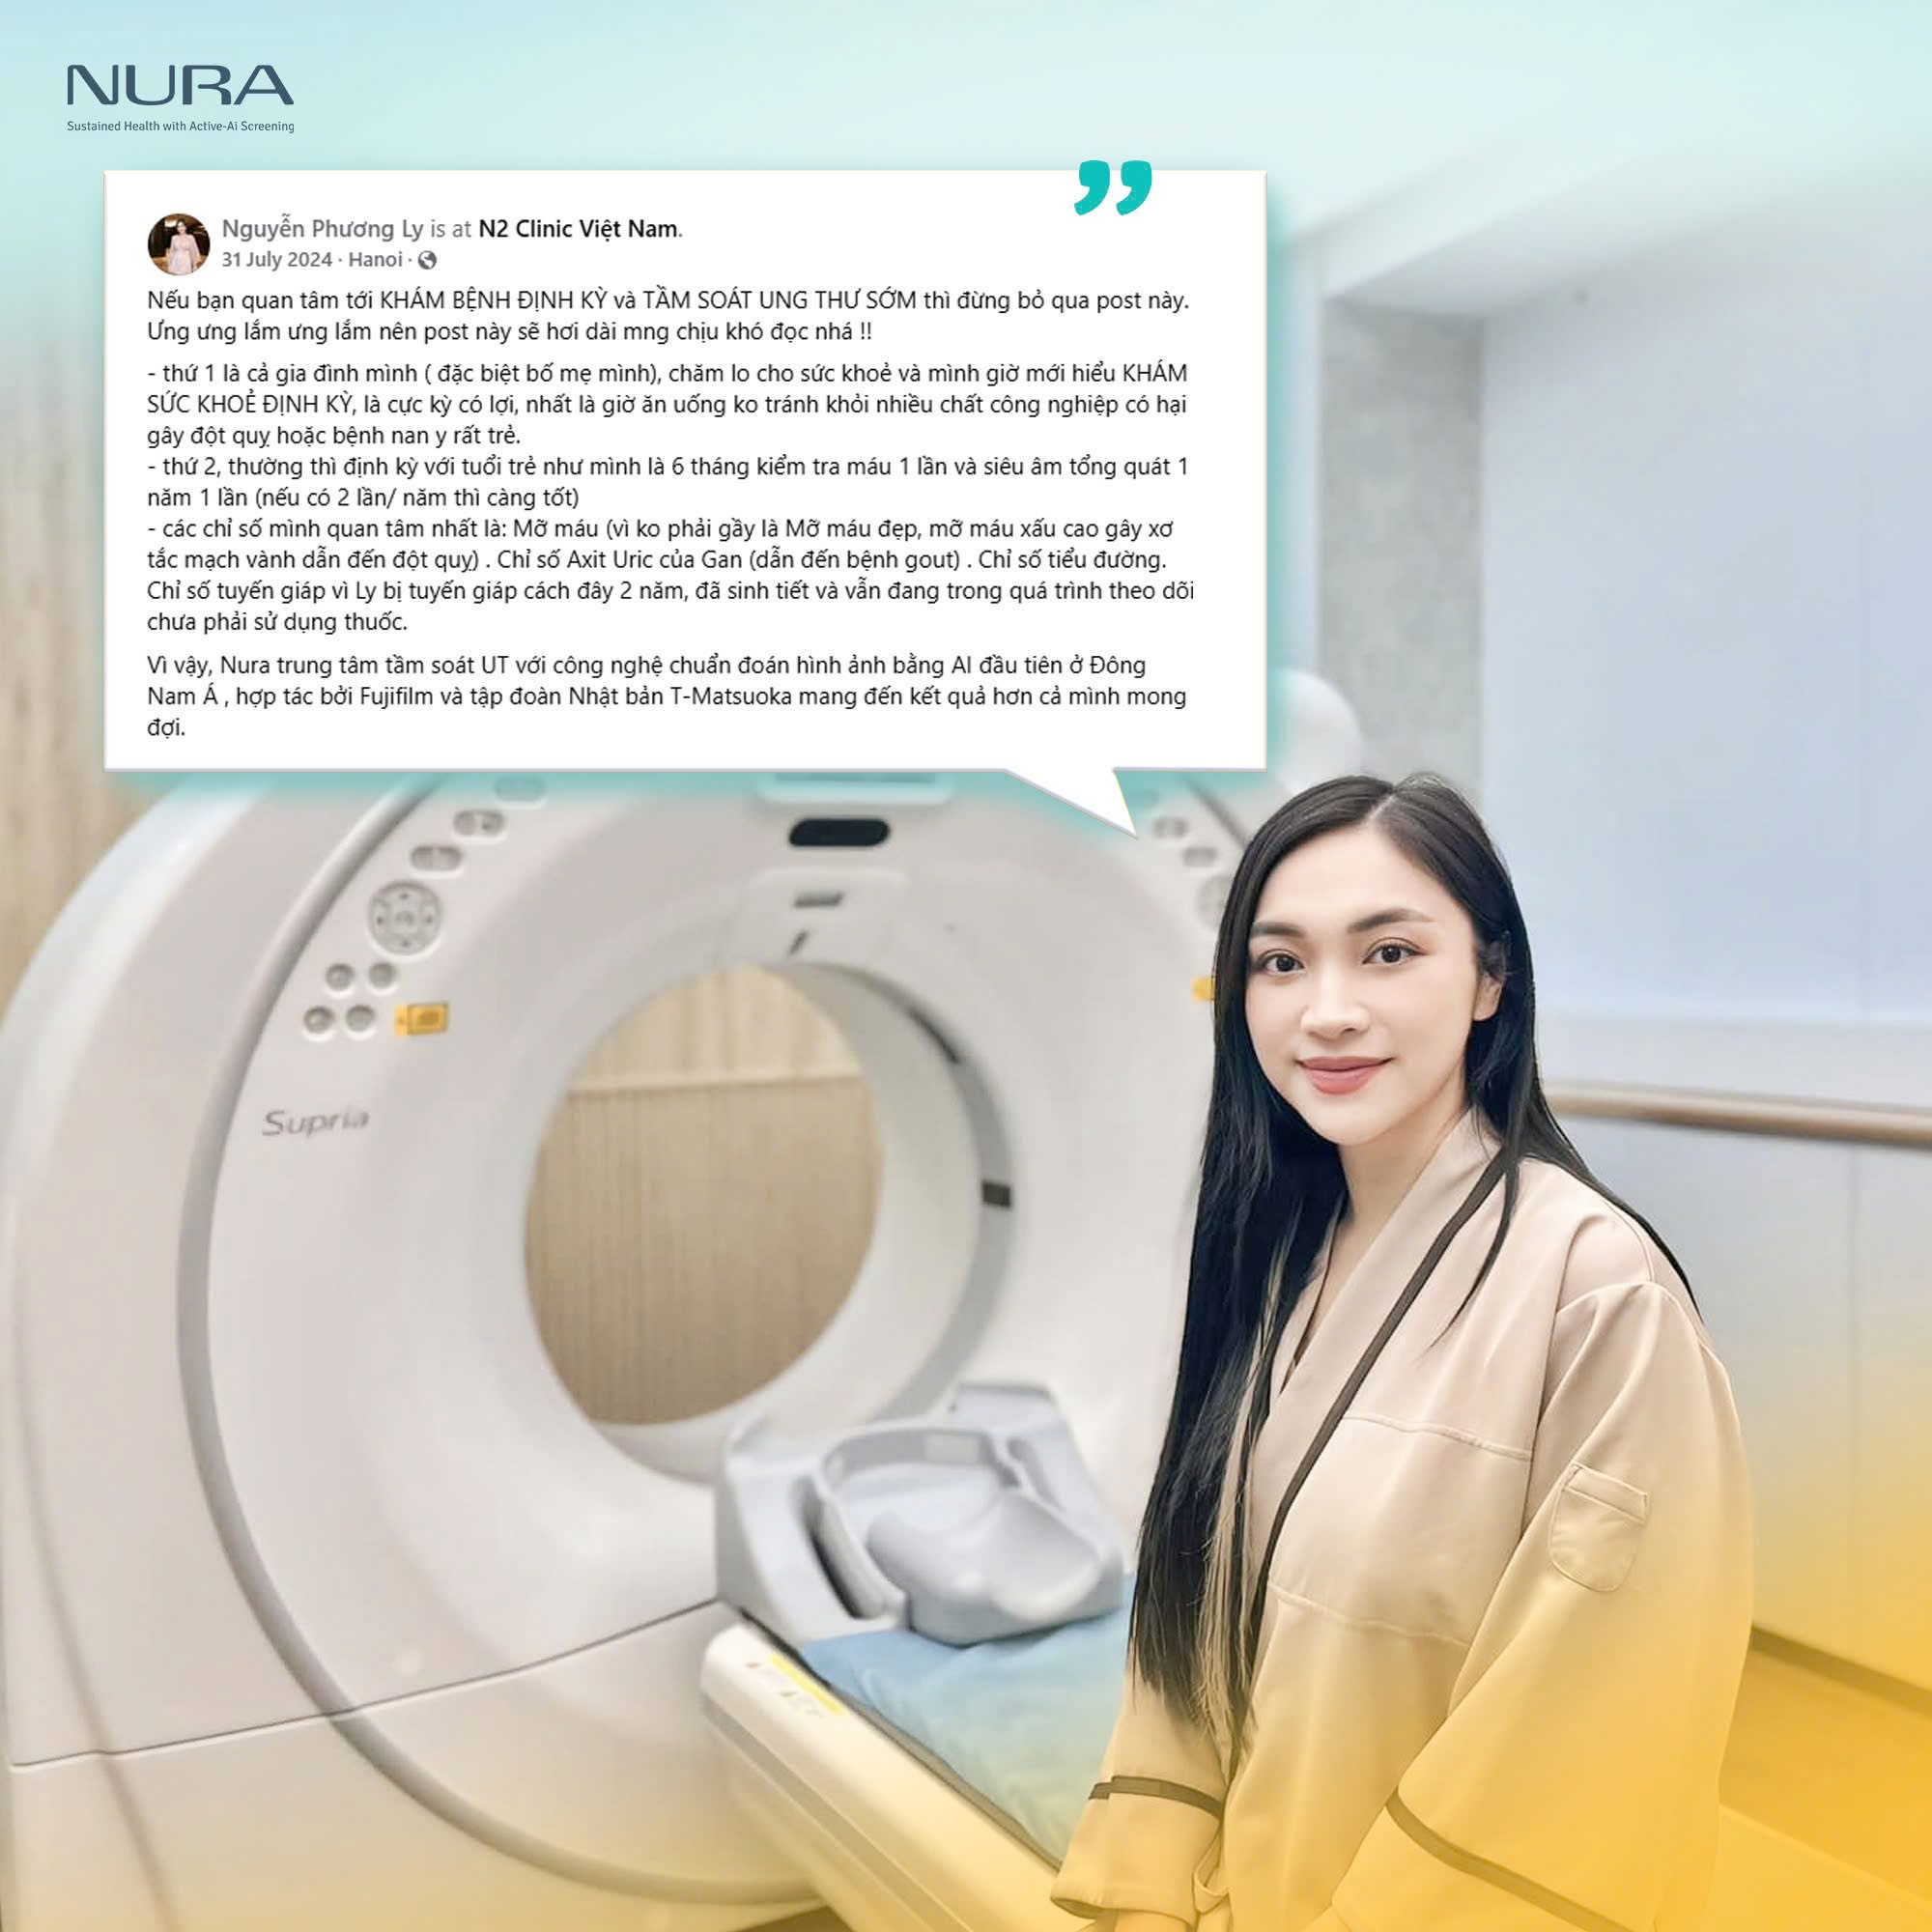

Một số hình ảnh khách hàng đánh giá về chất lượng dịch vụ tại NURA